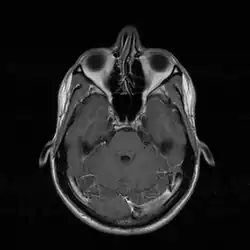

Transversales Schnittbild, oben im Bild sichtbar: Septumdeviation (im Bild nach links geneigt) (MRT-Aufnahme)

Septumdeviation (MRT-Aufnahme)